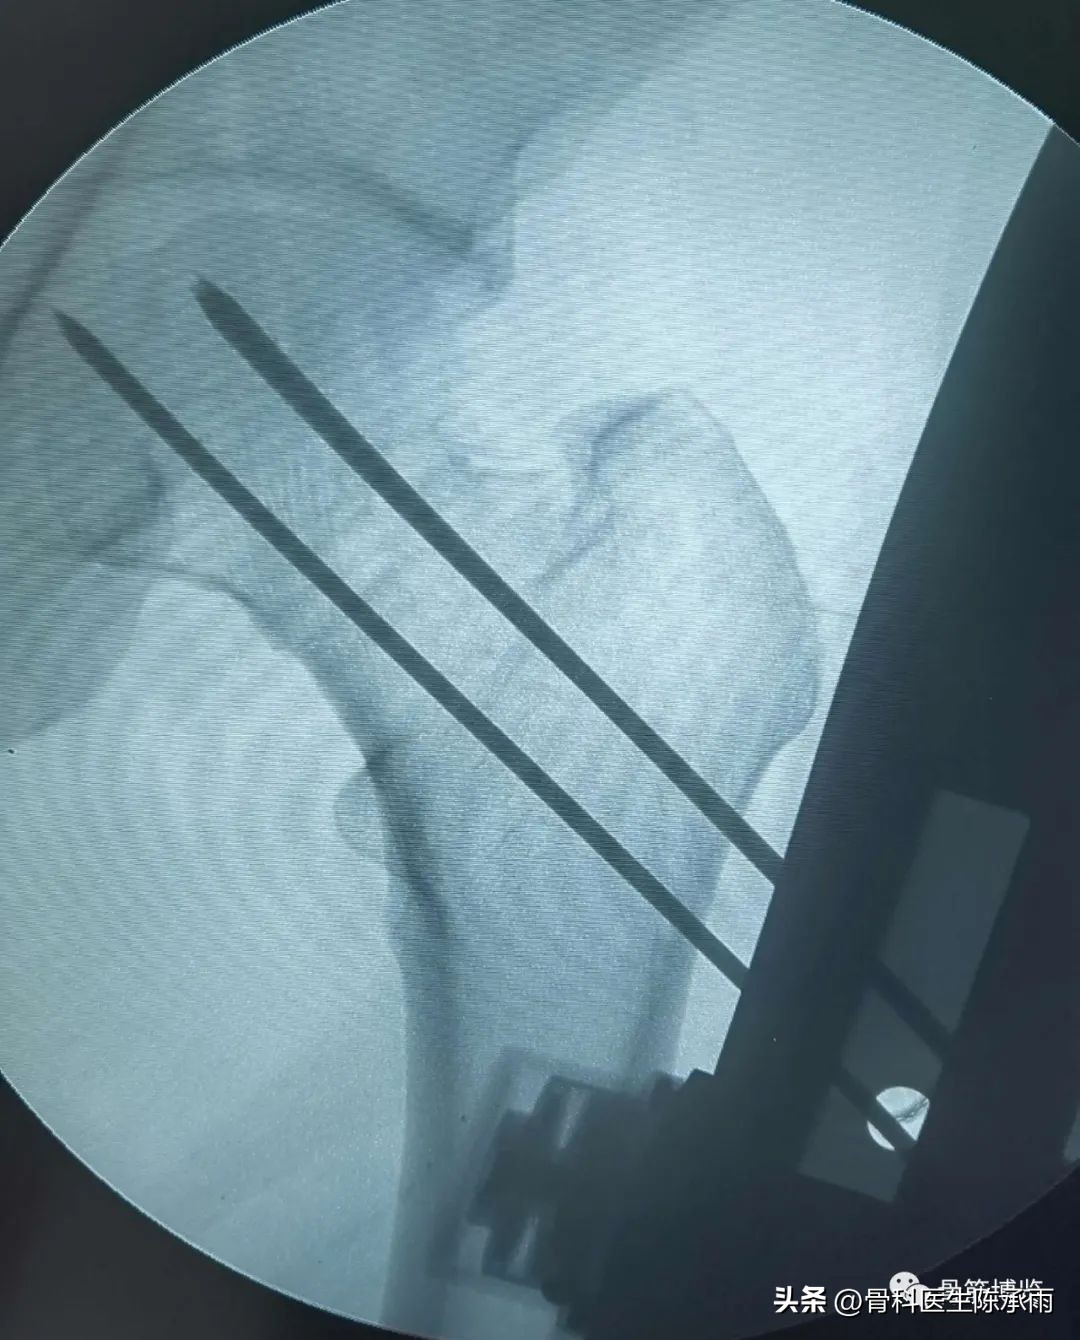

我们这例患者是一位脑瘫患者,患侧肢体短缩细小,股骨颈处及股骨髁上均做过截骨手术,失去了正常的角度,且股骨颈较细。给手术带来不小的难度。

术前尝试闭合复位,效果满意,决定行经皮穿钉,但股骨颈角度不正常,颈部细小,很难容得下3枚直径7.3空心钉,最后1枚空心钉部分切出股骨颈上缘。